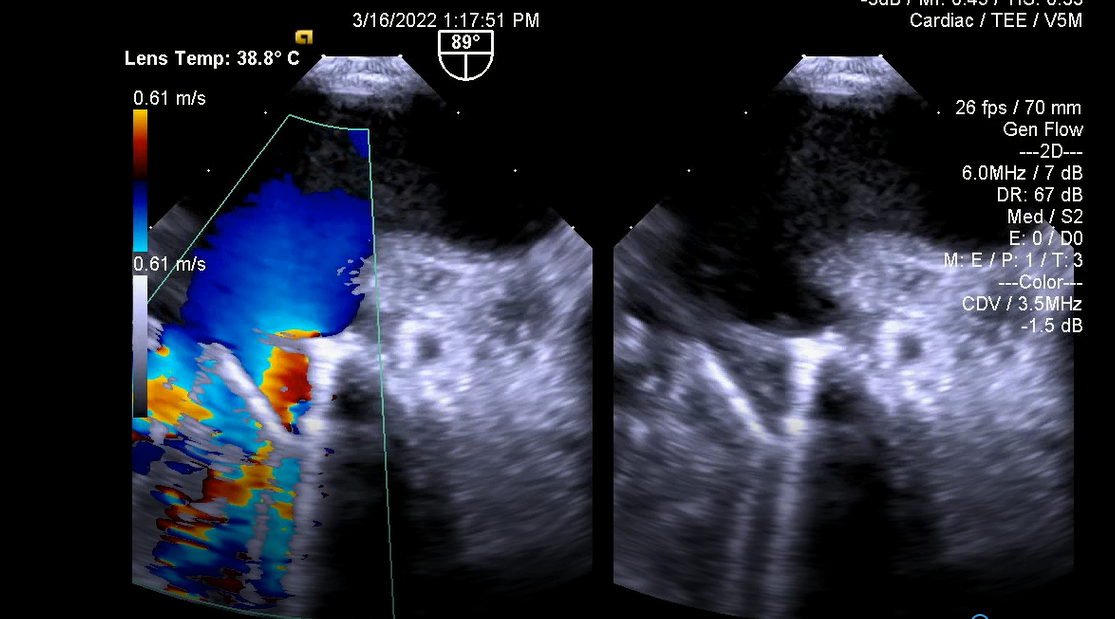

7.Dẫn đường hỗ trợ nong van hai lá bằng bóng

Trước nong van: